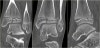

CT : 삼면 골절(The triplane fracture)

CT scan : 골절의 양상 및 관절내 전위 정도를 평가하는데 유용